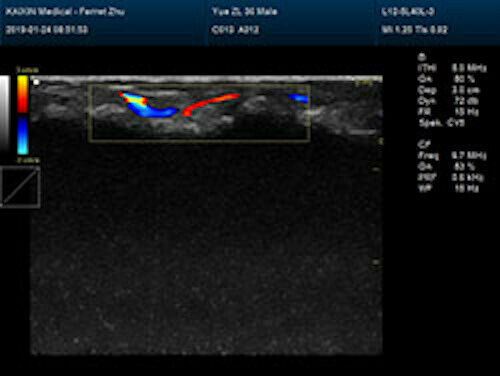

Large Animal Veterinary Color Doppler Ultrasound & Rectal Probe

| Powerful function & Configuration • Large screen display • Built-in lithium battery • Small size, light weight, easy to carry, N.W. ≤ 5kg • Equipped with a wide range of probes for abdominal, obstetric, vascular, cardiac, small organ, urinary applications • Built-in 4D module with optional 4D volume probe • A variety of digital peripheral interfaces, provides a variety of image output methods • PC platform, easy to operate, meet various software upgrades |

| Rich clinical application function • B+CF (Dual Images) • B+CF/PDI/DPDI+PW (Triplex) • Convex extended imaging technology • Linear array deflection/Trapezoidal imaging technology • Spatial compound Imaging technology • Panoramic imaging technology (optional) • 3D/4D imaging technology (optional) • Speckle noise removal technology • Pulse inversion tissue harmonic imaging technology (iTHI) |